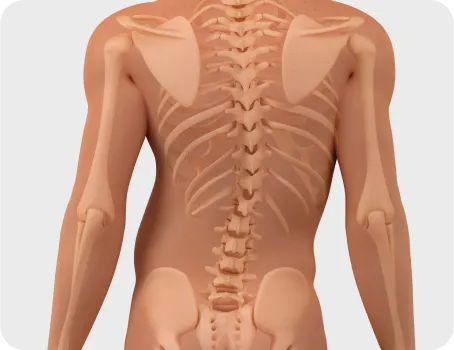

아픈 부위를 촬영한다고 진짜 아픈 원인을 찾을 수 없습니다.

실제 아픈 부위는 피해자일 가능성이 높습니다.

다리 저림이 문제라면 허리디스크 탈출을 의심하듯 무릎의 문제가 틀어진 발목이나 골반 때문일 수 있습니다.

그래서 가해자를 찾는 검사까지 같이 해야 합니다.

전신체형분석 X-선 검사

풀스파인 촬영으로

신체의 전체적인 문제를 파악하고

통증의 정확한 원인을 찾아

재발을 예방하고, 통증을 개선하는

치료를 합니다.

머리부터 발끝까지 완벽하게 체형을 분석 후 통증을 만들어낸 가해자가 누군지를 찾아내서 치료합니다.